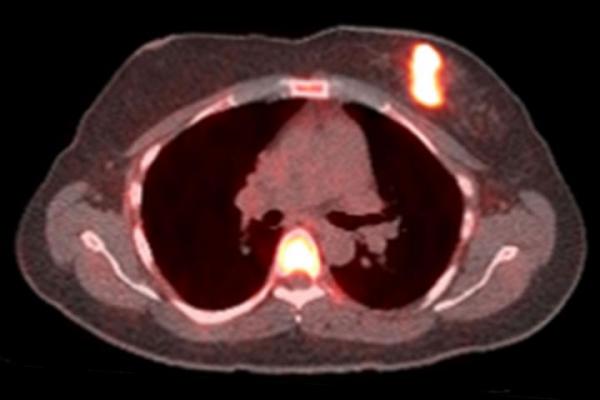

Bright spots indicate that cancer cells have responded to a one-day challenge with estrogen in this positron emission tomography (PET) scan of a woman with breast cancer. In a small study, researchers at Washington University School of Medicine in St. Louis found that only women whose tumors responded to estrogen challenge benefited from hormone therapy. The findings could help doctors choose the treatments most likely to help their patients. Image courtesy of Farrokh Dehdashti

The women underwent a PET scan using FFNP, followed by three doses of estrogen over a 24-hour period, and then a second PET scan a day after the estrogen treatment.

For 28 women, the PET signal in the tumor increased considerably after exposure to estrogen, indicating that their estrogen receptors were working and had responded to the hormone by triggering an increase in progesterone receptor numbers. Fifteen women showed little to no change in progesterone receptor numbers after estrogen treatment.